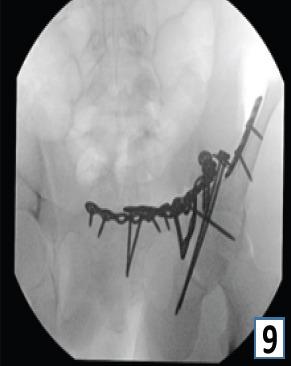

在此,我们报告一例16岁男性,有道路交通事故史,单纯闭合性左髋臼骨折。X线显示双侧髋臼柱骨折伴中心性半脱位。通过改良的Stoppa入路并带有外侧窗口对其进行切开复位内固定治疗。患者在受伤后第6天接受了ORIF。使用钢板和螺钉进行固定。在恢复室,他整个左上肢无法活动且无感觉,而手术肢体的远端神经血管功能正常。恢复15分钟后,感觉恢复,但运动功能障碍持续存在,提示臂丛神经失用。进行了脑部CT扫描,结果未见异常。6个月后,患者自行恢复了感觉,左上肢力量改善至5/5。

https://cdn.ncbi.nlm.nih.gov/pmc/blobs/99f1/12064220/be73f1751090/JOCR-15-43-g009.jpg